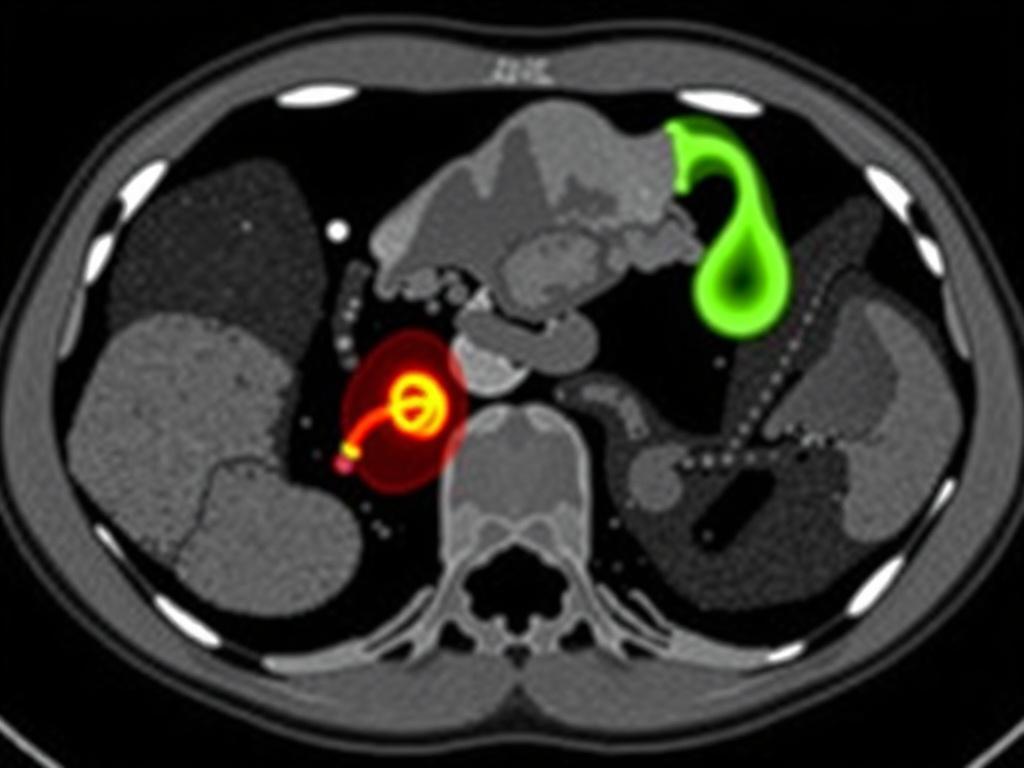

Dos tareas técnicas recurrentes son la segmentación (separar el apéndice y estructuras de interés del resto de la imagen) y la detección/classificación (decidir si hay apendicitis y su probabilidad). Para segmentación se usan U-Net y variantes 3D U-Net; para detección, arquitecturas basadas en CNN clásicas o modelos de clasificación más recientes. La segmentación también ayuda a medir el diámetro del apéndice y evaluar derrames periapendiculares de forma automatizada, ofreciendo métricas cuantitativas que refuerzan la interpretación clínica.

Modelos híbridos y ayudantes interpretables

La interpretabilidad es clave en medicina. Por eso muchos sistemas combinan modelos de imagen con reglas clínicas (edad, leucocitos, signos físicos) para mejorar predicciones y ofrecer explicaciones comprensibles. Herramientas de visualización como mapas de calor (saliency maps) muestran qué regiones de la TC influyeron en la decisión del modelo, ayudando al radiólogo a confiar y validar la recomendación automática.